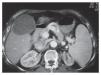

La evaluación de la respuesta al tratamiento se realizó por medio de tomografía computadorizada y marcadores tumorales. Se observó una respuesta total en 33.3% de los casos con evidencia de necrosis tumoral en más del 70% de la lesión mediante el uso de tomografía dinámica (Figura 2 y 3). En 66% de los pacientes hubo disminución significativa de los niveles séricos del marcador tumoral (alfa-fetoproteína o antígeno carcinoembrionario). Los niveles iniciales promedio de alfa-fetoproteina fueron de 169,122 ng/mL (rango 2 a 1 349 200 ng/mL) que contrastaron con los niveles promedio postratamiento de 35,081 ng/mL (rango: 2 a 463 000 ng/mL). Cabe mencionar que en esta serie de pacientes no se utilizó tratamiento neoadyuvante o adyuvante.

Figura 2. Tomografía de hígado donde se observa hepatocarcinoma unifocal en el segmento IV del hígado al momento del diagnóstico

Figura 3. Tomografía de hígado donde se observa al mismo paciente un mes después de la ablación por radiofrecuencia